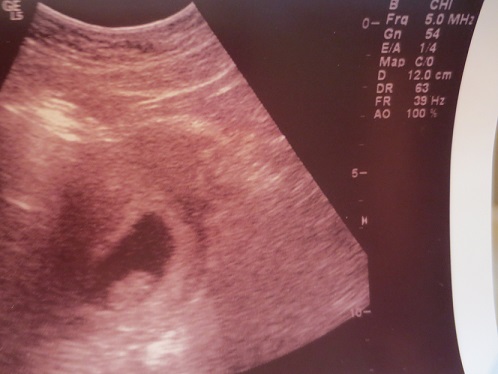

This was taken at 8 1/2 weeks abdominally not sure if it should be flipped or not how it was shown on the u/s screen is how the pic looks. U/S was to find HB after coming in for spotting.